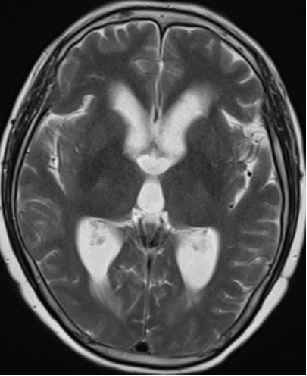

2015-4-1 MRI

2015-3-31

脑压100